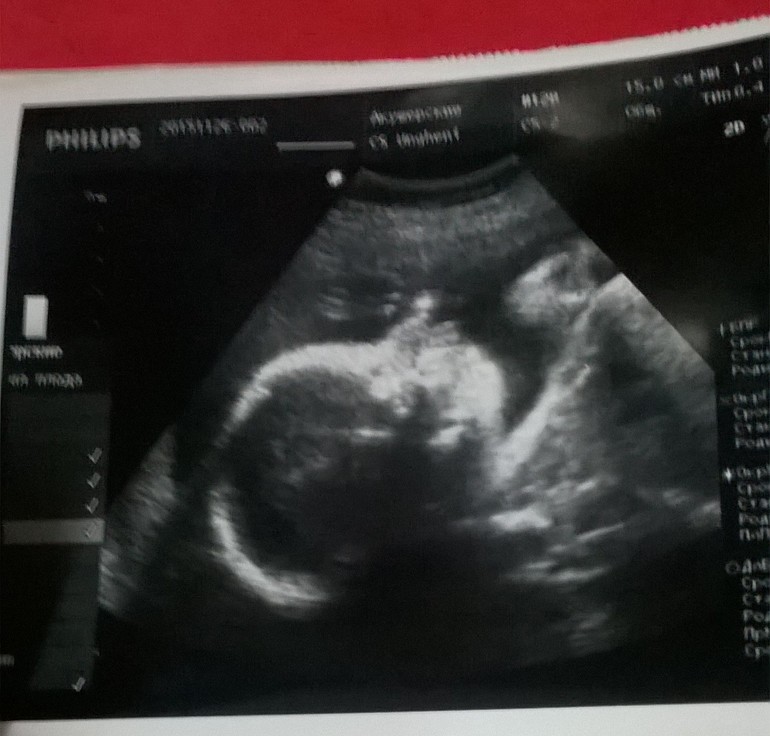

Результаты: УЗИ, КТГ, доплера, скринингаВчера в обед сынуля пнул меня сильно и притих.Вечером тишина, ночью тишина, утром опять тишина(( Я испугалась не на шутку.. Обычно он утром и вечером активничал и ночью когда вставала в туалет. Пошла в ЖК с утра. Стою в очередь к гине, подошла моя очередь и тут зашла какая- то женщина с ребенком маленьким,видимо знакомая, и давай они там хи-хи, ха-ха, минут 20. Я тут стою чуть ли не плачу, а они ржут там.. Зашла наконец-то, начала говорить в чем дело и плакать начала.Успокоили меня и повели сразу на УЗИ. Я лежала и ждала ну когда же что-то скажут(( Она молчит, говорит одевайся, и только потом сказала, что все хорошо) И даже распечатала фото) Я пришла домой вся в слезах, муж испугался. Я легла рядом с ним он прислонился к животику и просил сына пнуть меня, чтоб я перестала плакать. И он пнулся)) И сейчас толкается)) И я наконец-то успокоилась) Сынулька, не пугай нас так больше, пожалуйста!